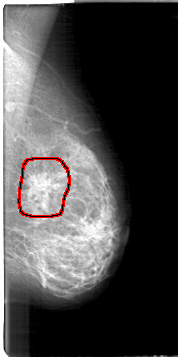

D_4106_1.LEFT_CC

LEFT_CC LINES 4666 PIXELS_PER_LINE 2611 BITS_PER_PIXEL 12 RESOLUTION 43.5 OVERLAY

FILE: D_4106_1.LEFT_CC.OVERLAY

TOTAL_ABNORMALITIES 1

ABNORMALITY 1

LESION_TYPE MASS SHAPE IRREGULAR MARGINS SPICULATED

ASSESSMENT 5

SUBTLETY 4

PATHOLOGY MALIGNANT

TOTAL_OUTLINES 1

BOUNDARY